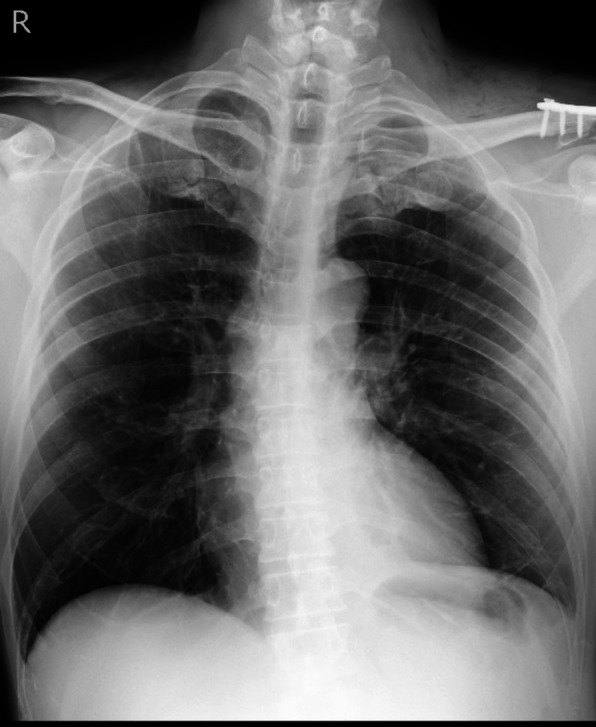

A man in his 50 s with no significant medical history (height 177 cm, weight 73 kg) presented to the emergency department with left shoulder pain after a bicycle fall. Imaging revealed fractures of the left clavicle and the left second and third ribs. While the chest radiograph did not show any obvious pneumothorax (Fig. 1A), CT demonstrated a mild left-sided pneumothorax (Fig. 1B). There was no significant hemothorax, pulmonary contusion, or subcutaneous emphysema. Given the absence of respiratory symptoms, a conservative approach without chest tube placement was adopted. Follow-up chest radiography and CT the next day confirmed that there was no progression of the pneumothorax. Surgical fixation of the clavicle fracture was scheduled for post-injury day 6.

Fig. 1.

Chest radiography (A) showed no obvious pneumothorax, while computed tomography (B) revealed a mild left-sided pneumothorax